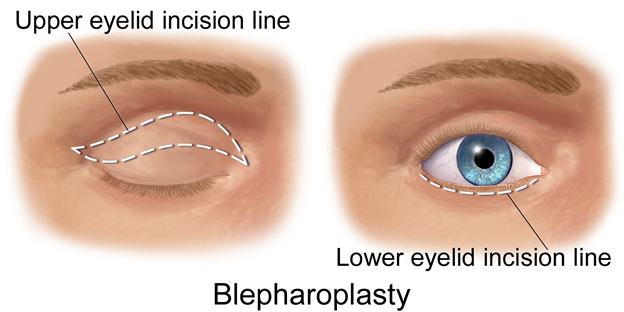

Upper Blepharoplasty

This surgery removes excess skin, fat, or muscle from the upper eyelids to create a more youthful and alert appearance.Overview

Incisions are made along the natural upper eyelid crease.Excess skin and sometimes fat are removed or repositioned.

The incision is closed with fine sutures for minimal scarring.

Pros:

Refreshes eyelid appearance, making eyes look more open and alertCan improve vision if excess skin obstructs the field

Minimal visible scarring when done along the crease

Cons:

Swelling and bruising for 1–2 weeksRisk of asymmetry or overcorrection

Not a solution for droopy eyelids caused by weak muscles (ptosis)

UPPER BLEPHARO BEFORE & AFTER